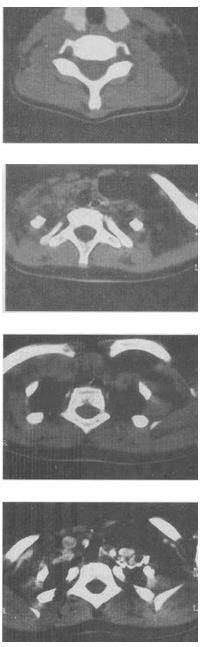

- 单项选择题 女,17岁,发现左侧颈部包块半年余,PE://病灶质软,境界不清,无压痛,CT如图所示,最可能的诊断是()。

D、颈部淋巴管瘤